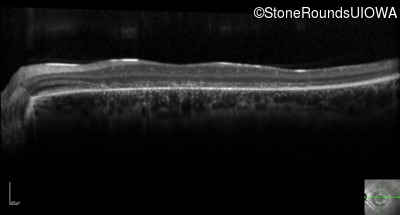

Optical Coherence Tomography - Right - 20/200 -3

Exemplar / OCT Stack

OCT Stack